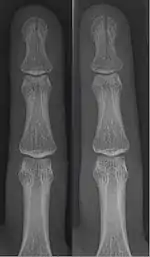

- Broken finger – a fracture of the carpal phalanges

![]() In the fingertip. More images |

Linear fracture | Parallel to the bone's long axis | ||